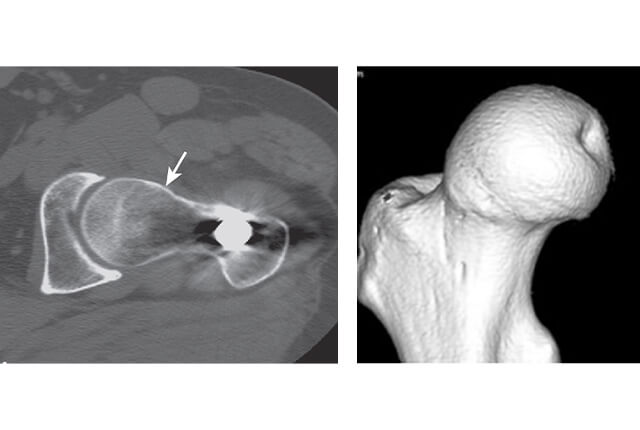

レントゲン、MRI、CT図4

レントゲン、MRI、CT(図4)